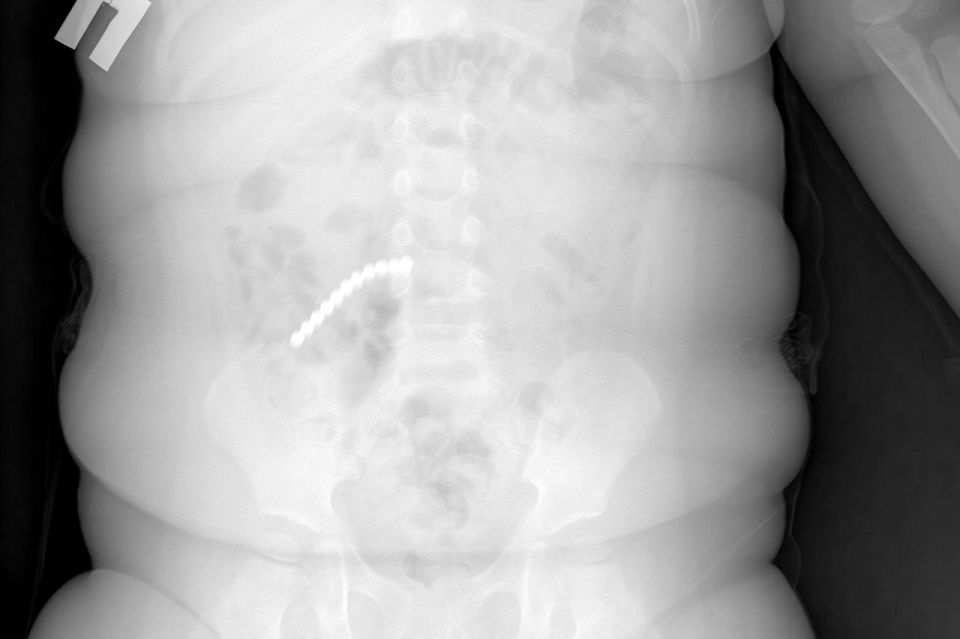

Сначала родители думали - отравление или вирус. Но когда сделали рентген, врачи увидели страшное. Почти весь кишечник был усеян мелкими шариками. Как выяснилось, пациент проглотил 20 шариков от магнитного конструктора - неокуба.Девять деталей врачам...